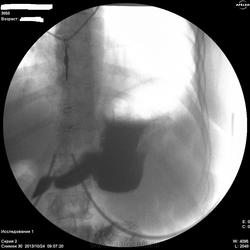

По-желудку - расположен косопоперечно, в гипертонусе. Впечатление не полного тугого наполнения. На большой кривизне могут быть и складки, плохо видно. На малой кривизне похоже на 2 ниши, ширина которых преобладает над глубыной, могут быть онкологические, но опять же куда они деваются на последнем снимке... Пилорический отдел либо конически сужен, либо не наполнен адекватно. В общем, можно просто предположить, либо это язвеная болезнь "хроническая" (отсюда деформация желудка и все остальное), либо это онкология (лимфома к примеру). Либо вообще такую картину дает гипертонус, усиленная перистальтика и малое количество контраста. Предложил бы искусственную гипотонию и бария не менее 200 мл.

Жалоб конкретных нет(так,что-то ноет).Еть отрывки кинопетли лёжа,но сегодня не смогу показать.Первый кадр здесь-стоя,потом-с поворотами налево и направо.Я собственно снимки не делаю,пишу кино.В "последующих сериях" деффект сохранялся,на компрессию не реагировал.

Первые три-в орто.Последний-лёжа.